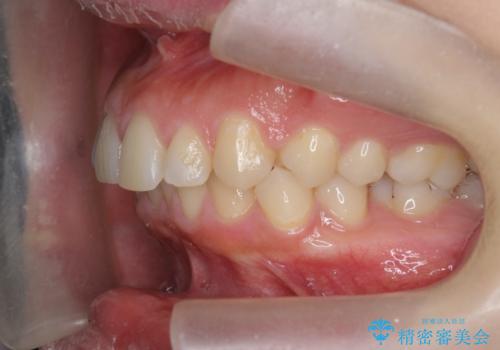

深い噛み合わせ、すきっ歯の改善 ワイヤーを用いたマルチブラケット矯正

- 噛み合わせが深く、前歯が突き出て隙間が出てきたことの改善を希望され矯正治療の相談で当院に初診来院されました。

ワイヤーを用いたマルチブラケット矯正を行うことで深い噛み合わせを改善し、前歯の隙間もなくし審美的な歯列へと治療をおこなっていきます。

深い噛み合わせの改善は前歯の圧下が必要なため、治療期間が長期化することが多いです。